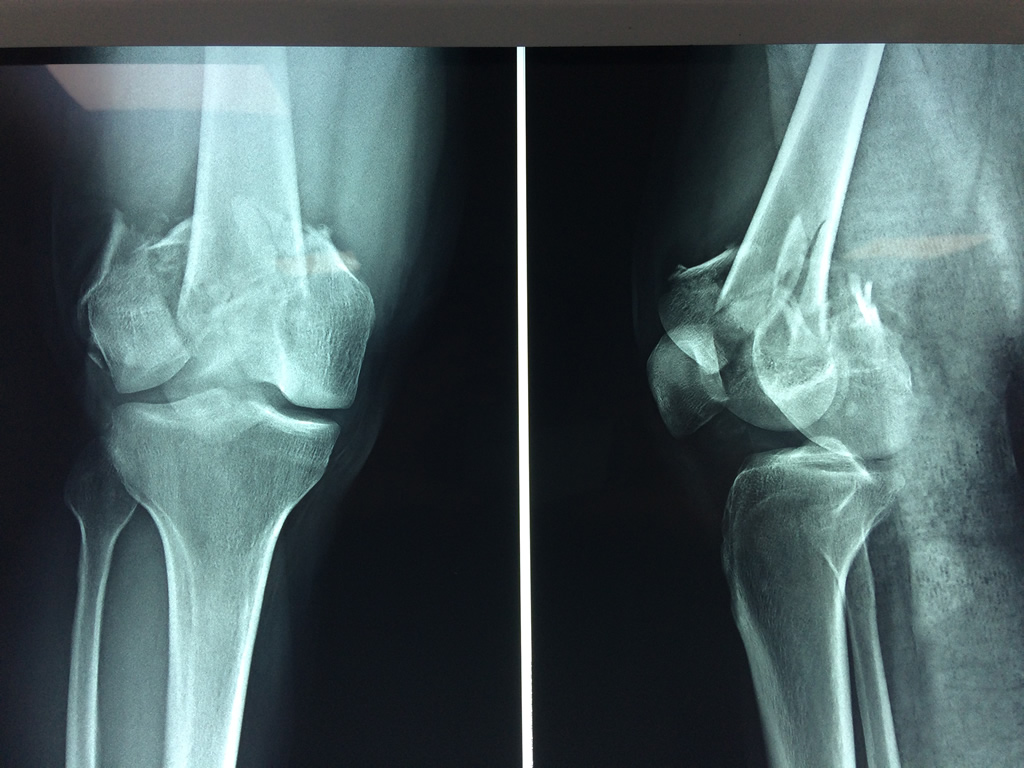

Cirugía de Rodillas

El fémur es el hueso del muslo, el segundo segmento del miembro inferior. Es el hueso más largo, fuerte y voluminoso del cuerpo humano.